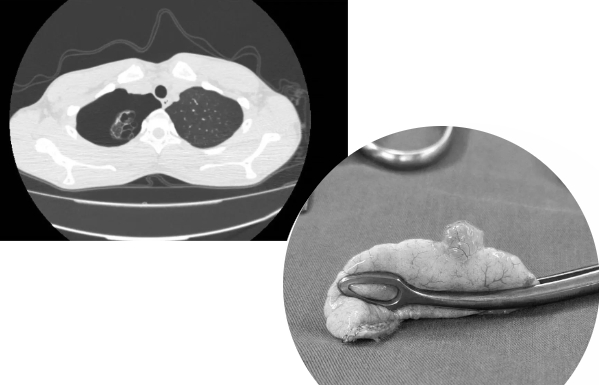

肺大疱常见于双肺肺尖表面,因青春期胸廓和肺的生长发育速度差距过大,导致肺尖等张力过大处的表面肺组织发育畸变,进而形成肺大疱。若在剧烈运动后出现胸腔内刺痛、胸闷、咳嗽等症状,应高度警惕肺大疱破裂导致的自发性气胸的可能性。

●若经影像学检查积气量不多(肺压缩不超过30%),可考虑暂保守观察。

有可能会复发。在不处理原发病灶(肺大疱)的情况下,患者出院后再次复发的概率很高。因此,对于自发性气胸后发现存在明显肺大疱的患者,建议前往胸外科手术干预。目前,国内微创胸腔镜技术已经相当成熟,对于被肺大疱和自发性气胸困扰的运动青年来讲,通过5天左右的短期住院手术治疗即可出院。